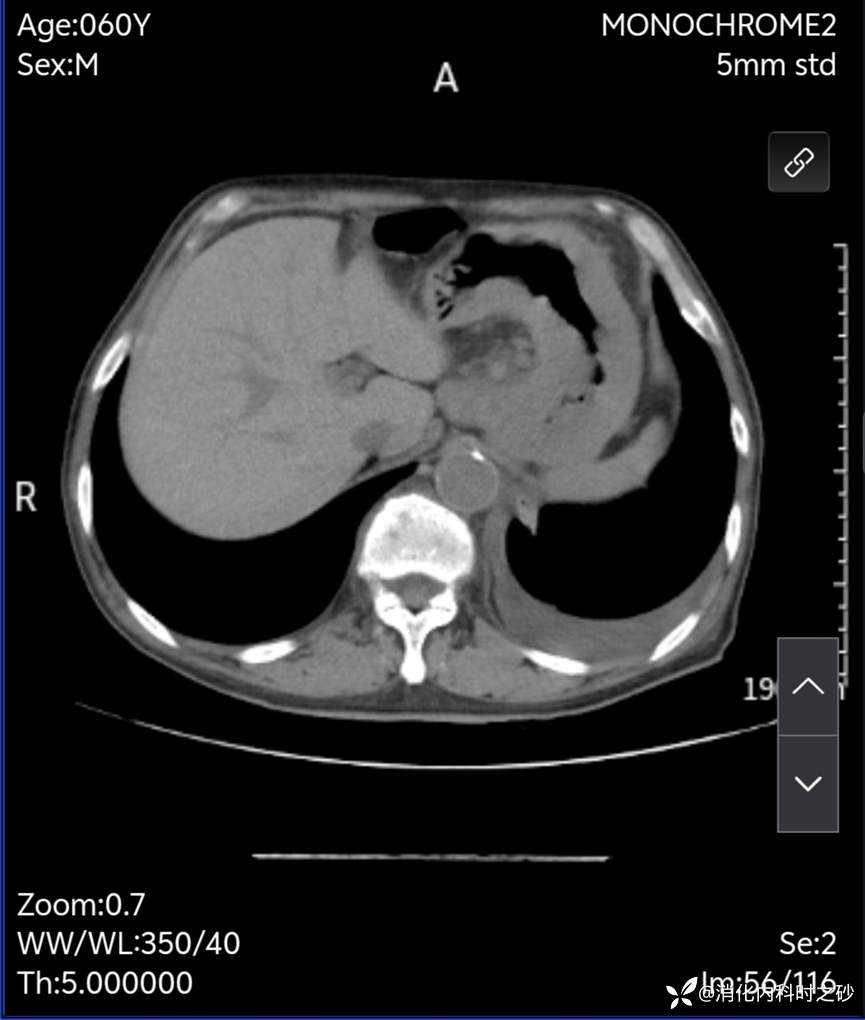

腹部CT示:胃壁增厚,小网膜囊区多发增大淋巴结